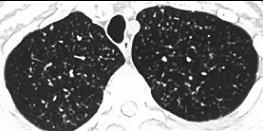

问题 女,23岁,消瘦盗汗1月余,干咳1周,偶痰中带血,影像如图,最可能的诊断为 ( )

选项 A、慢性支气管炎 B、SLE肺部侵犯 C、含铁血黄素沉着 D、弥漫性肺纤维化 E、粟粒性肺结核

答案 E